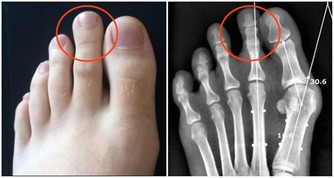

8.腰腿影響肝腎

我們都清楚腰不好就是腎虛的表現,因此來說腰靈活,那麼反之就是腎氣十分的充足。

而腿腳好的話則就是肝血旺盛的表示。想要腰腿靈活,那麼平時的運動非常的重要。